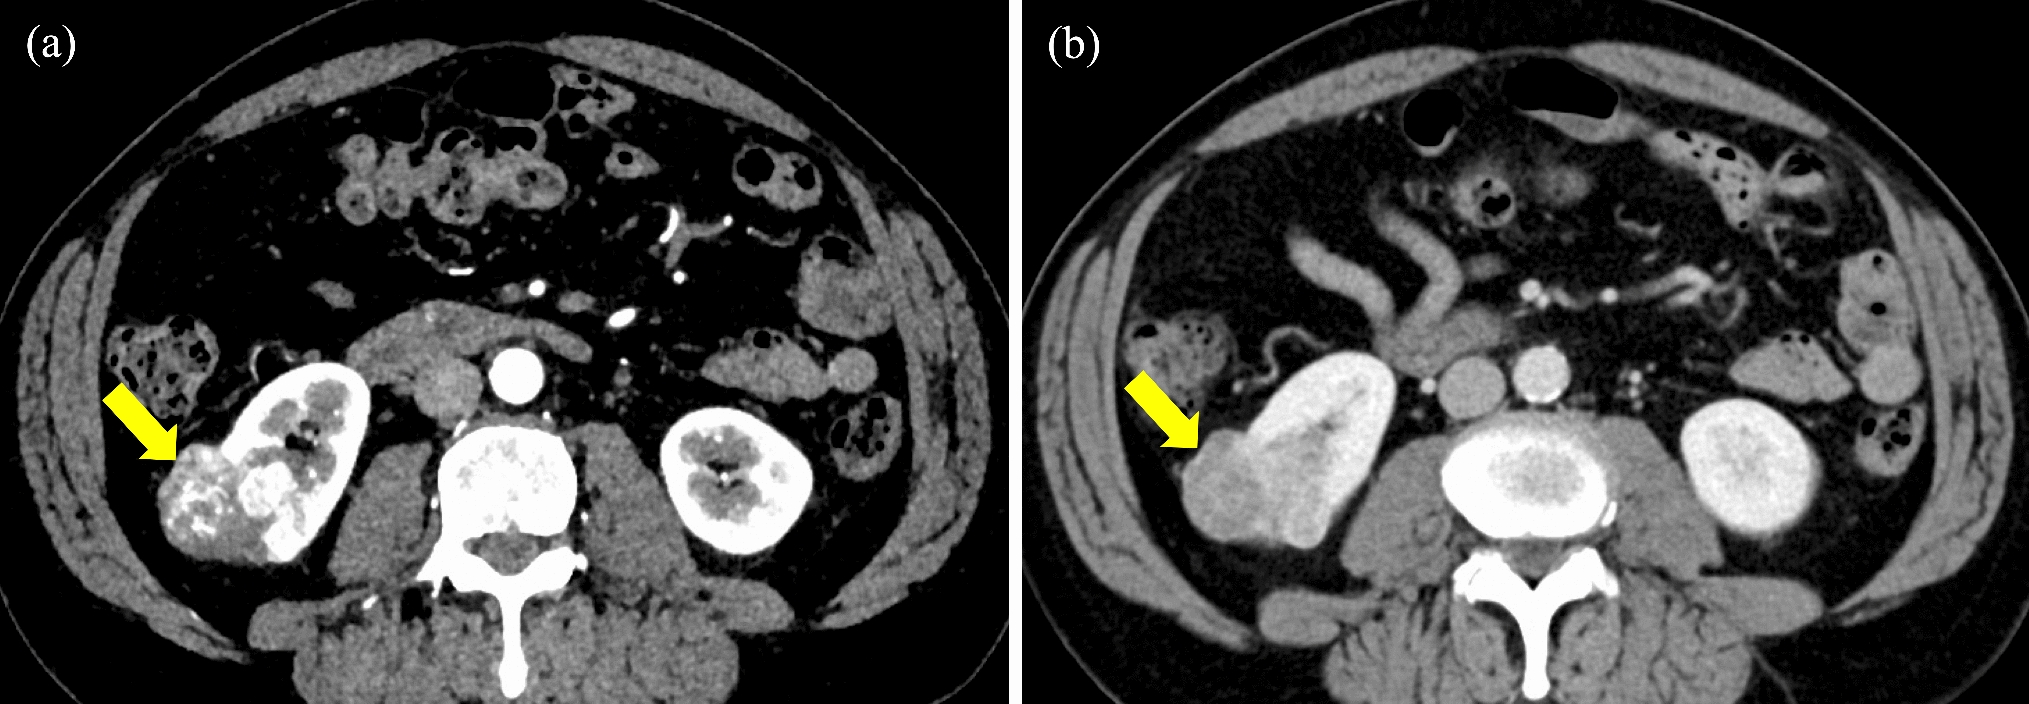

Stereotactic body radiation therapy (SBRT) is the standard treatment for patients who are medically inoperable or who refuse surgery with stage I non-small cell lung cancer (NSCLC). While acute lymphopenia following SBRT is documented, the long-term effects on the immune system and infectious disease remain unclear. In this report, we present two cases of chronic progressive pulmonary aspergillosis (CPPA) occurring within the irradiated field following SBRT for inoperable stage I NSCLC. Case 1 was a man in his 70 s with a history of smoking and a previous pulmonary resection and SBRT for metachronous primary lung cancer. He received SBRT for T1aN0M0 NSCLC in the right lower lobe as his third primary lung cancer. After 20 months, the patient developed a cough and sputum, and a computed tomography (CT) scan revealed a cavity shadow in the irradiated field, which led to the diagnosis of CPPA. Intravenous voriconazole was immediately started, and after 3 week’s administration, the symptoms improved, and the cavity disappeared. After 34 months, the patient died with no recurrence of CPPA and lung cancer. Case 2 was a man in his 80 s with a history of smoking and previous pulmonary resection for lung cancer. He received SBRT for T1cN0M0 NSCLC in the right lower lobe as his second primary lung cancer. After 19 months, the patient developed a fever, and a CT scan revealed a cavity shadow in the irradiated field, which led to the diagnosis of CPPA. Oral itraconazole was administered, followed by diarrhea and anorexia. After 22 days, the patient died. During the follow-up period, there was no recurrence of lung cancer. Risk factors for CPPA include a history of smoking and lung resection, common among candidates for pulmonary SBRT. When a cavity shadow develops following SBRT, differentiating consolidation as radiation pneumonitis, local recurrence, or infection can be challenging. When a cavity is identified on a follow-up CT scan after SBRT, it is crucial to include CPPA in the differential diagnosis.